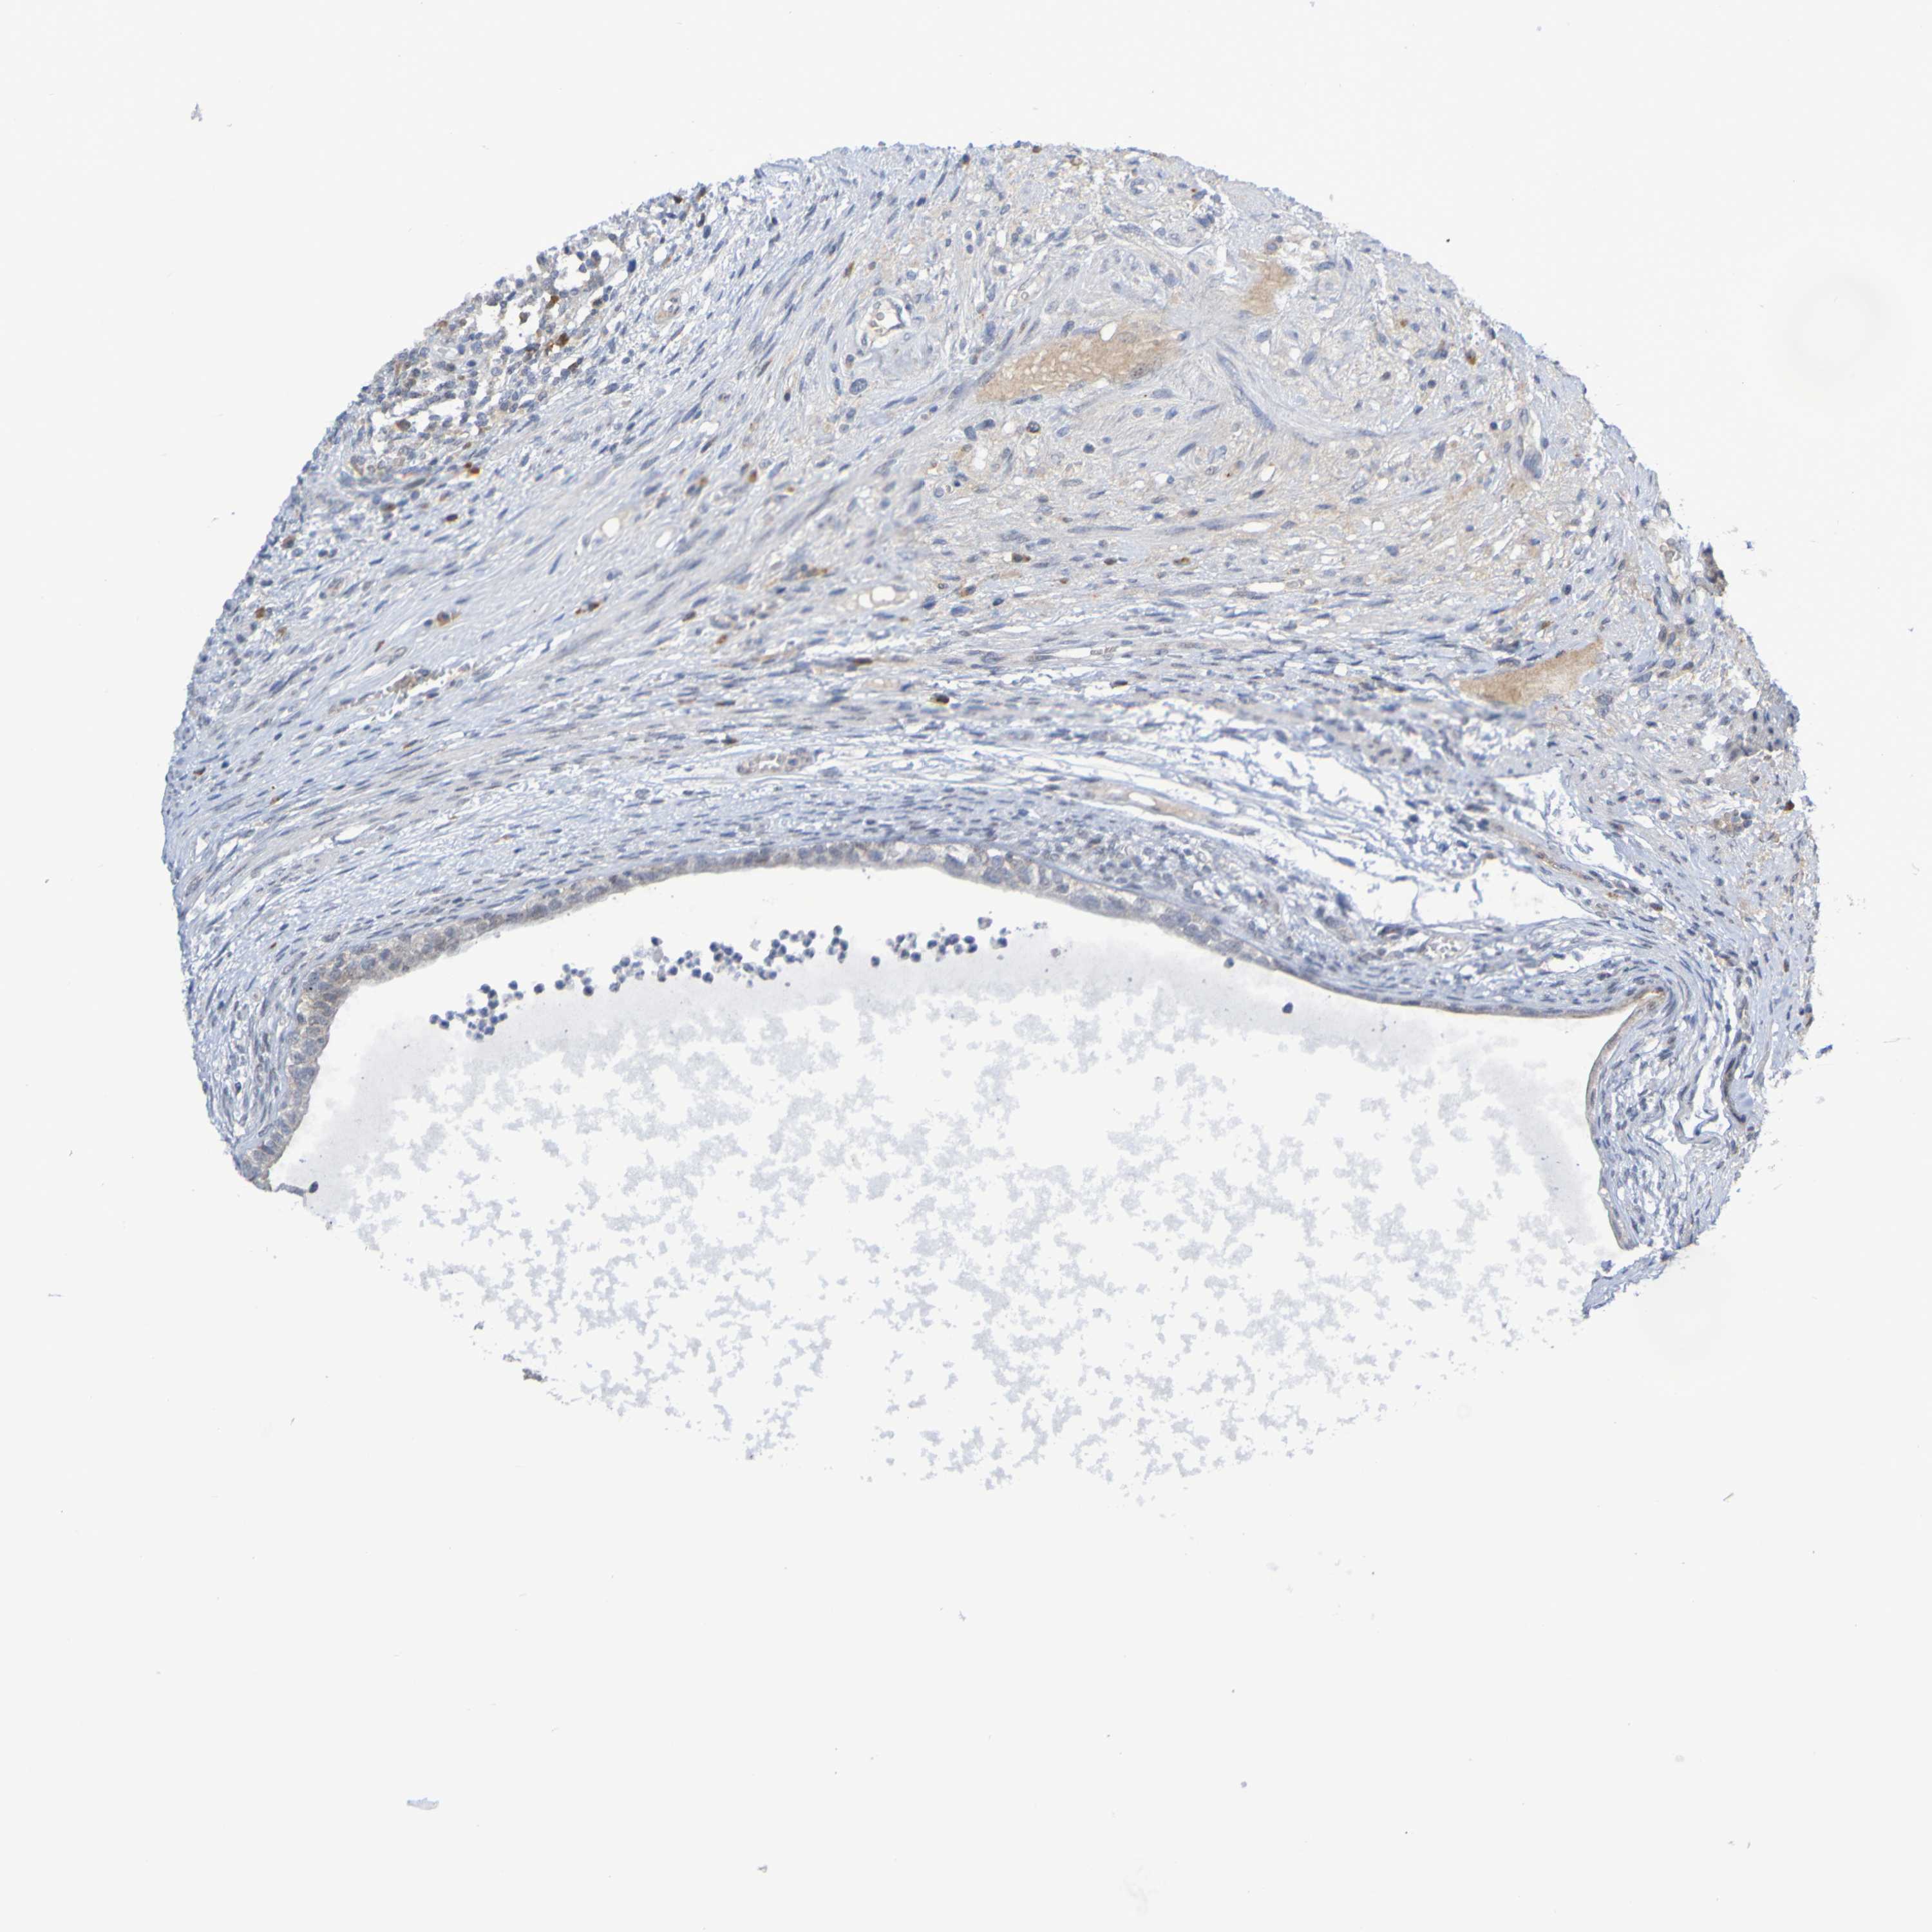

TESTIS CANCER - Protein expressioni

A mouse-over function shows sample information and annotation data. Click on an image to view it in a full screen mode. Samples can be filtered based on level of antibody staining by selecting one or several of the following categories: high, medium, low and not detected. The assay and annotation is described here.

Note that samples used for immunohistochemistry by the Human Protein Atlas do not correspond to samples in the TCGA dataset.

Antibody stainingi

Antibody staining in the annotated cell types in the current human tissue is reported as not detected, low, medium, or high, based on conventional immunohistochemistry profiling in selected tissues. This score is based on the combination of the staining intensity and fraction of stained cells.

Each image is clickable and will lead to virtual microscopy that enables deeper exploration of all samples and also displays staining intensity scores, fraction scores and subcellular localization as well as patient and tissue information for each sample.

Antibody HPA063275

Antibody HPA067326

Antibody CAB012652

Seminoma, NOS

Carcinoma, Embryonal, NOS